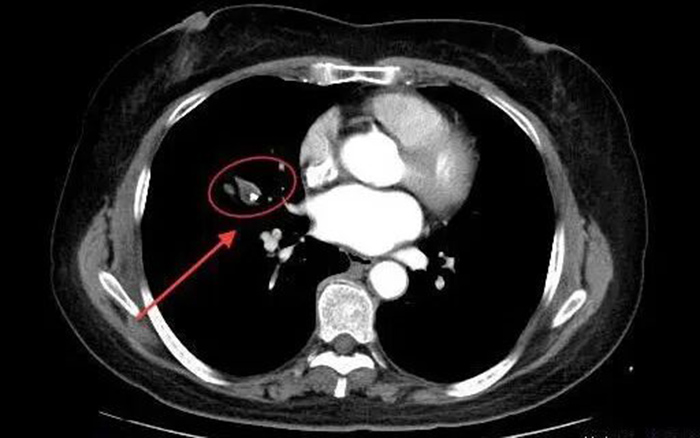

影像检查中,右肺支气管中疑似卡堵异物

周边组织也已出现炎性病变 在完善相关检查后,我院呼吸与危重症医学科医疗团队发现:蒋阿姨的肺部存在双肺结节影、纵隔及左肺钙化灶、主动脉粥样硬化等情况。同时,右肺支气管中有一团炎性病变组织,包裹着异物,疑似造成了支气管卡堵。